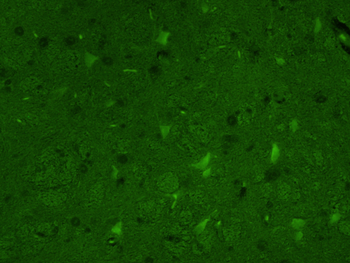

IF, IHC-Fr, IHC-P, WB

应用稀释比例:WB=1:500-2000, IHC-P=1:100-500, IHC-F=1:100-500, IF=1:100-500